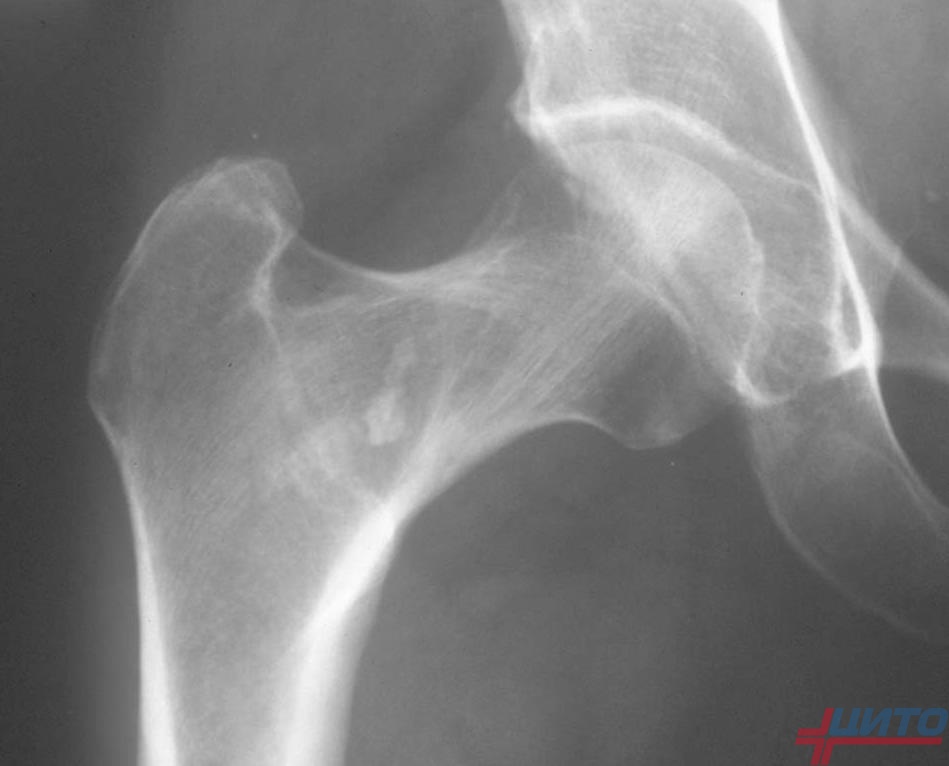

| Рентгенография шейного отдела | Это основной метод для подтверждения диагноза. Снимки в нескольких проекциях (прямой, боковой, с функциональными пробами) позволяют увидеть сросшиеся позвонки, оценить их количество и локализацию, выявить нестабильность позвоночных сегментов. |

| Компьютерная томография (КТ) | Назначается для детальной оценки костных структур. КТ создает трехмерное изображение позвоночника, что помогает хирургам точно спланировать оперативное вмешательство, если оно необходимо. |